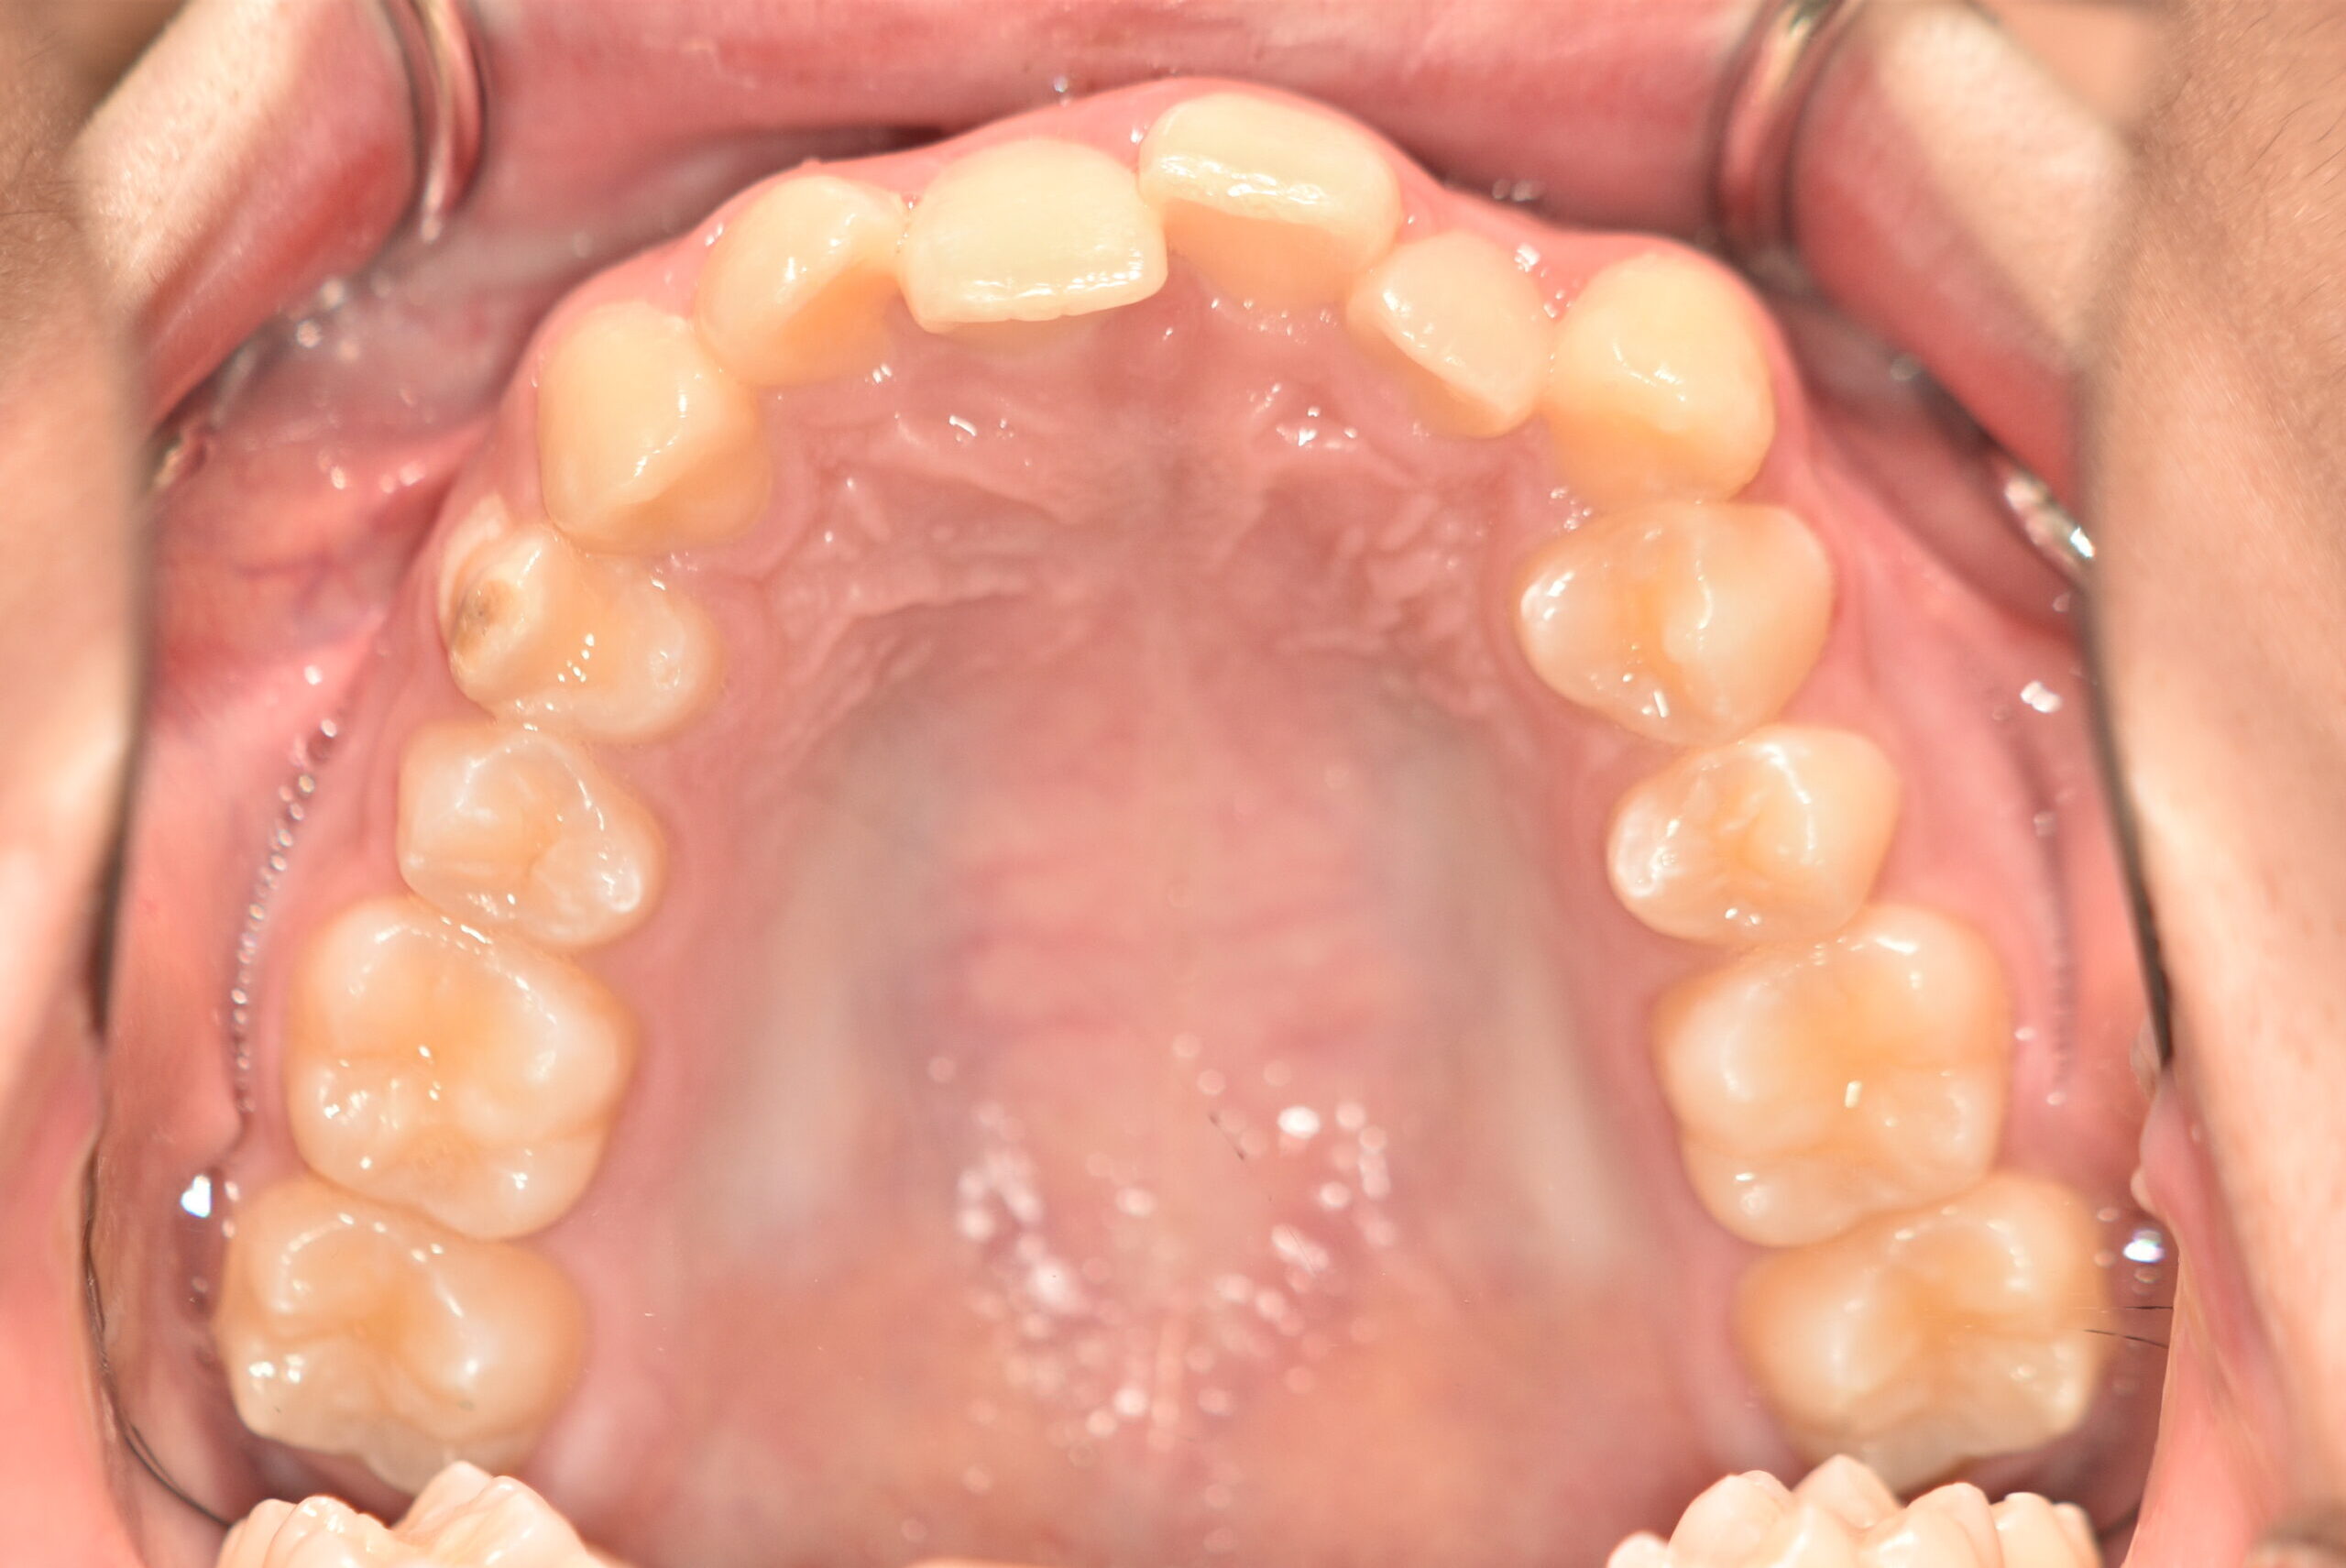

| 治療内容の詳細 | 初診時16歳の男性で、歯のがたつき、かみ合わせを気にされ来院しました。 検査の結果、アングルⅡ級2類不正咬合と診断しました。 治療としては、非抜歯の上、セルフライゲーションブラケット装置(デーモンシステム)で配列を行いました。 同時に顎間ゴムにて咬合関係の改善を行いました。 治療期間は、1年6ヶ月でした。 |